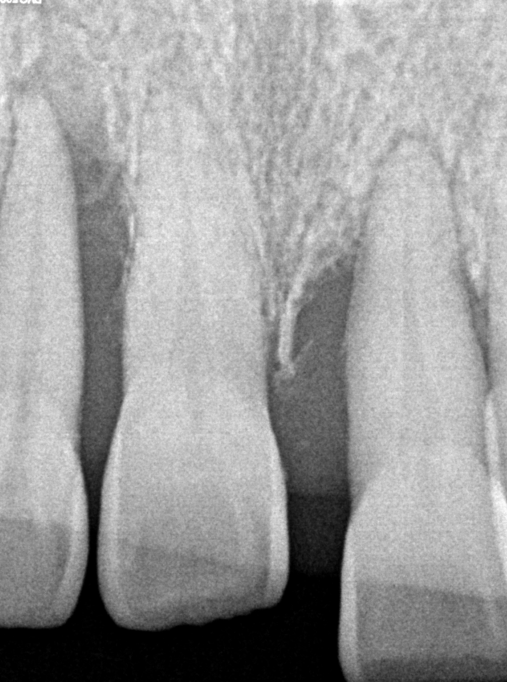

파노라마 및 CBCT 분석 결과,

* 전반적인 만성 치주염 소견

* 상·하악 치조골의 광범위한 흡수

* 특히 상악 전치부에서 수직·수평적 골 소실이 현저

* 치근 대비 잔존골 높이 및 폭 모두 제한적

즉, 환자가 느끼는 불편은 앞니였으나

실제 문제는 이미 치조골 단계에서 진행 중인 상태였다.